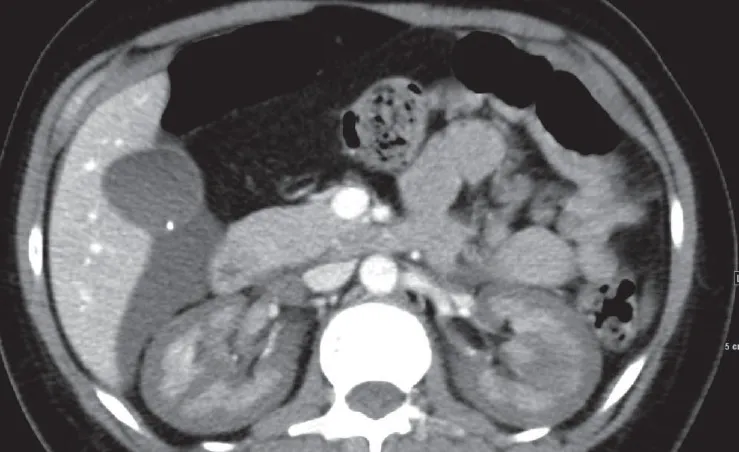

IRA + Icterícia: Um Caso que Exige Investigação Detalhada

IRA + Icterícia: Um Caso que Exige Investigação Detalhada